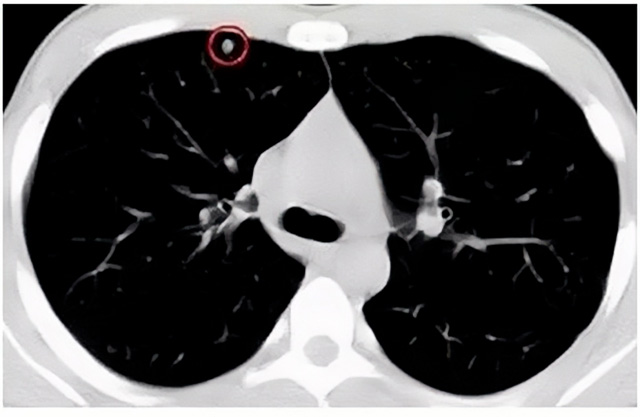

移动CT体检车可以检查肺结节发现早期肺癌

移动CT体检车可以做肺部检查。随着多层螺旋CT肺部低剂量扫描的临床应用,目前很多人选择肺部CT作为常规检查项目,较大地提高了肺结节的检出率。如果检查发现肺部有肺结节是磨玻璃型的,小于5mm的微小结节,大部分都是良性的。如果达到1CM以上的,很有可能有肺癌的机率。根据其内密度不同可分为磨玻璃结节、实性结节、部分实性结节。根据其大小可分为肺大结节、小结节和微小结节。如果是炎症性肺结节,几个月后复查有变化变小就不用做手术。如果CT再次复查结节没有变化,没有缩小就需要升级做病例检查。病理检查的确诊性是最高的。是有没患癌的标准。检查发现早的话,规范手术治疗,手术后5年的存活率很高的。肺癌这个要早发现早治疗。

现在的移动CT体检车的分辨率比X光高,CT扫描的图像越来越薄显像更清晰,检查更准确。得到了普及,肺结节的测出率很高的。但是ky体育网页入口登录告诉大家,肺结节不等于肺癌。虽然很多是良性,但是很多肺癌都是肺结节发展来的。 必须定期检查复查。磨玻璃结节,肺癌的机率较高。肺癌是恶性肿瘤病死率最高的。除了环境,遗传,等因素。吸烟,从事烟雾工作行业的人员比较危险。发病比例高。肺部疾病早发现早治疗,依旧是肺部疾病的治疗标准。

一旦CT检查发现肺结节,若不规律复查,检查等同于白检。所以在复查中,如果结节中发现有增大的趋势,或大小发生了变化,我们必须提请注意及时治疗,不要掉以轻心。移动CT体检车的普及化,让肺部检查更准确更高效。发现肺结节时,及时就医并进行专业评估是确保准确分类和采取适当措施的关键。